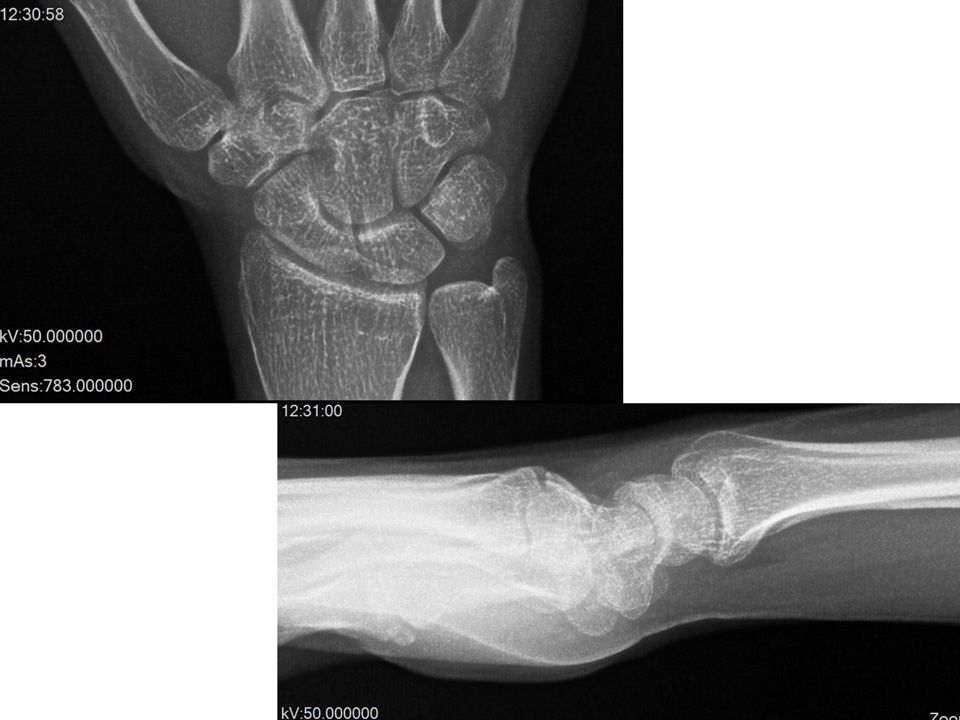

27 yaş, erkek, makineci (tekstil)3 yıldır her iki el bileğinde fizik tedaviye rağmen geçmeyen ağrıSol el bileğinde SL eklem dorsalinde, anatomik enfiye çukuru üzerinde hassasiyet